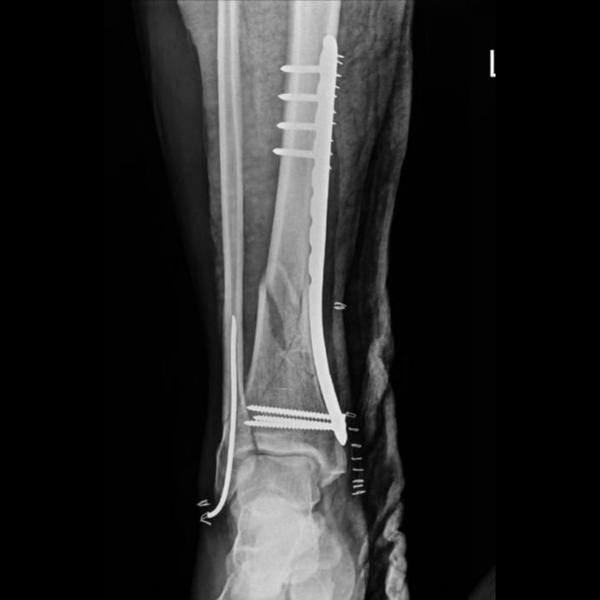

Type 6 Schatzker Tibial Condyle fracture 4 months post op .Patient walking full weight bearing.